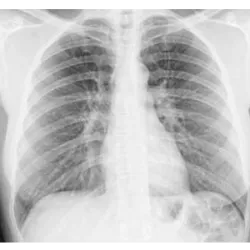

El 5 de enero es el Día de la Abreugrafía en Brasil y rinde homenaje a la técnica de abreugrafía, una prueba de imagen utilizada para detectar enfermedades pulmonares, como la tuberculosis. Esta fecha es importante para resaltar los avances en la medicina y las prácticas de prevención de la salud, especialmente en la detección temprana de enfermedades respiratorias.

La abreugrafía fue desarrollada por el médico brasileño Ely Correa Abreu, quien a principios del siglo XX creó un método más accesible y sencillo de realizar radiografías de tórax, facilitando la detección de enfermedades como la tuberculosis. La prueba se ha convertido en una herramienta importante para las campañas de salud pública, especialmente en la lucha contra la tuberculosis en Brasil.